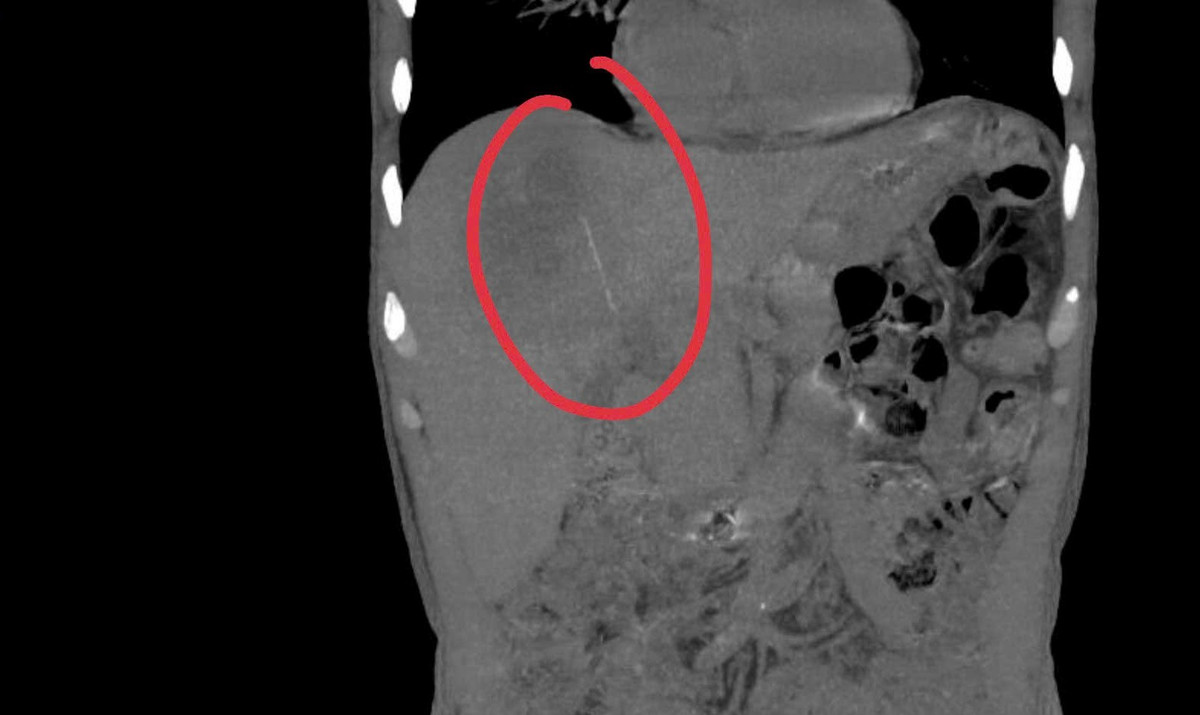

Kết quả cho thấy có một dị vật dạng que dài nằm hoàn toàn trong nhu mô gan, kèm theo ổ áp xe sâu. Trước nguy cơ biến chứng nặng nếu không điều trị kịp thời, ê-kíp khoa Nội tiêu hóa đã nhanh chóng hội chẩn cùng khoa Ngoại Gan Mật Tụy, thống nhất phương án phẫu thuật lấy dị vật, dẫn lưu ổ áp xe, kết hợp điều trị kháng sinh phù hợp.

Chia sẻ về sự phức tạp của ca bệnh này, ThS BS Trần Đình Quốc, Khoa Ngoại Gan Mật Tụy cho biết, ca phẫu thuật gặp nhiều khó khăn do ổ áp xe nằm sâu trong nhu mô gan, vị trí gần cơ hoành và các mạch máu lớn.

Ban đầu dự kiến sẽ tiến hành phẫu thuật nội soi cho bệnh nhân nhưng buộc phải chuyển phương pháp mổ để có thể tiếp cận an toàn, xử lý ổ áp xe và lấy dị vật. Thời gian phẫu thuật vì vậy cũng kéo dài gấp đôi so với các ca áp xe gan thông thường.